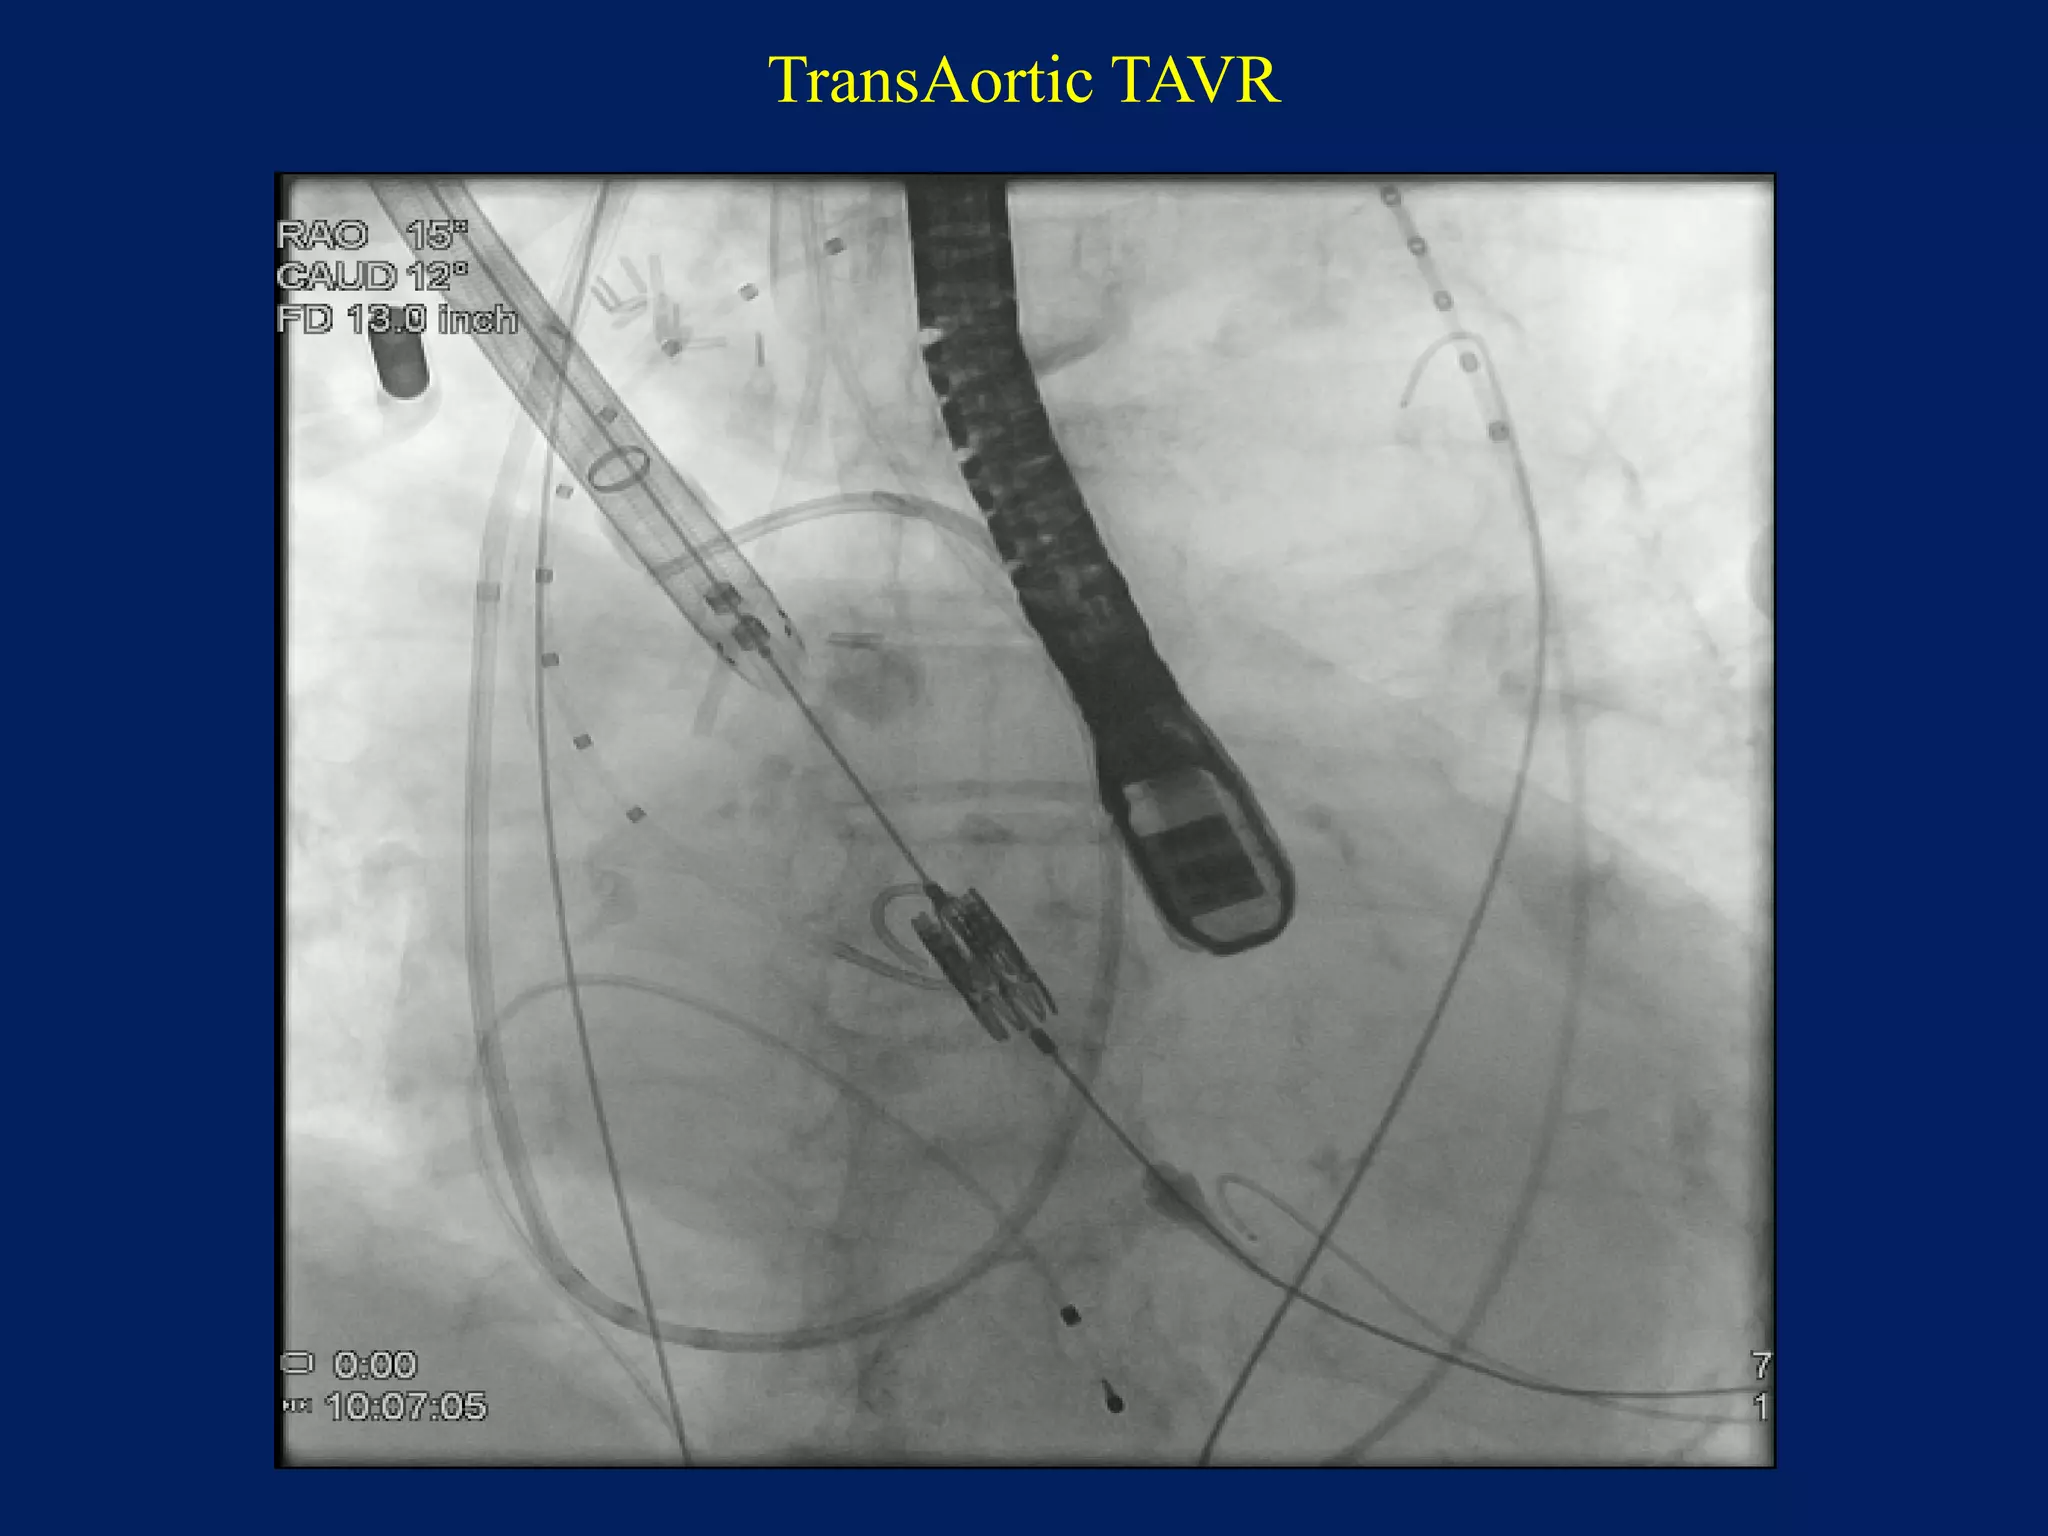

TransAortic TAVR